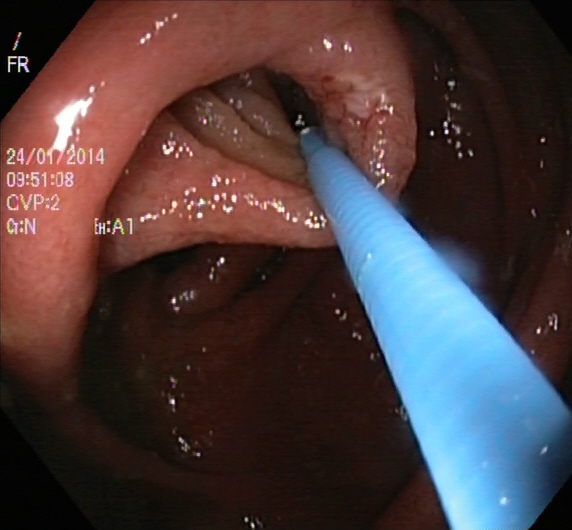

Figure 1. Sample images of GI findings. Each image represents one of the 16 classes from the dataset used for the Medico 2018 challenge (Pogorelov et al., 2017c, a).